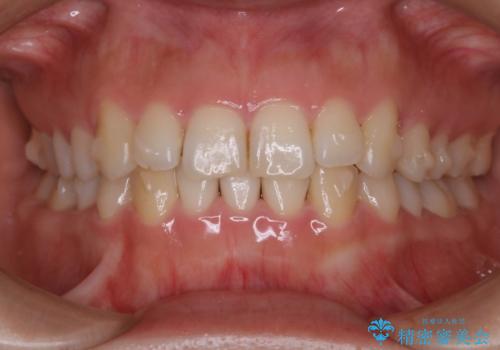

- 前歯のがたつきが気になるとのことで来院されました。

上顎の真ん中の歯の角度が、内側に傾いており、またその隣の歯が、唇側にずれてしまっていました。

下顎については、前歯にがたつきがありました。